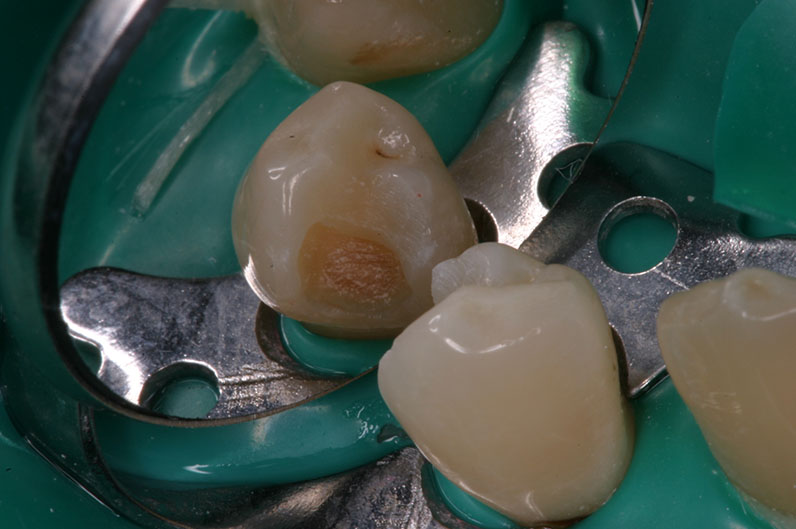

Proface* provides a clinical aid in the detection of bacterially infected hard tooth tissue, particularly infected dentin. This way, caries excavation is more reliable than with traditional tools (probing the hardness, application of staining agents). The traditional tools only indirectly permit a conclusion on the bacterial infection of dentin. By contrast, the Proface* light probe, together with the diagnostic goggles, form a tool which can be used to directly visualize the remaining bacterially infected dentin (referred to below as residual caries) at any time and to evaluate the success of the caries excavation.

The Proface* light probe uses the so-called FACE (Fluorescence Aided Caries Excavation) method, which has been proven in different clinical studies.

before excavation

with Proface*

wth Proface*

without Proface*

after excavation